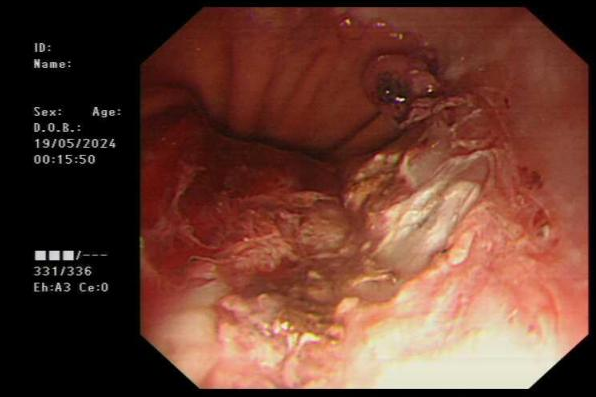

郑XX,女性,47岁,因“黑便、呕血半天”入院。入院行胃镜检查提示十二指肠球部溃疡血管残端裸露,为Forrest IIa级出血,有内镜下止血指征。消化内科团队为患者行内镜下十二指肠球部溃疡裸露血管残端电凝止血术,经对症治疗后患者已出院。

十二指肠球部溃疡血管残端裸露

电凝止血